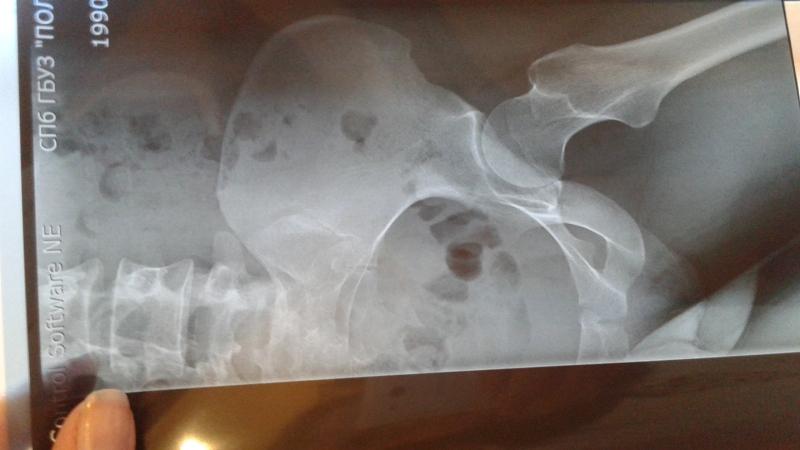

Инструментальные методы диагностики охватывают такие процедуры, как рентгенография, компьютерная томография (КТ) и магнитно-резонансная томография (МРТ).

К примеру, результаты рентгенографического исследования при анкилозирующем спондилоартрите (болезни Бехтерева) на первой стадии показывают увеличение суставной щели с умеренным субхондрозом, на второй стадии – уменьшение щели с выраженным субхондрозом и незначительными эрозиями.

При «ревматическом» сакроилеите можно наблюдать уменьшение щели воспалённого сустава или её полное отсутствие, а также нечеткость и неровность контуров суставных поверхностей и увеличение плотности костной ткани.

При неспецифическом сакроилеите, напротив, чаще всего фиксируется снижение плотности костной ткани в крестцово-подвздошных сочленениях и увеличение суставной щели.